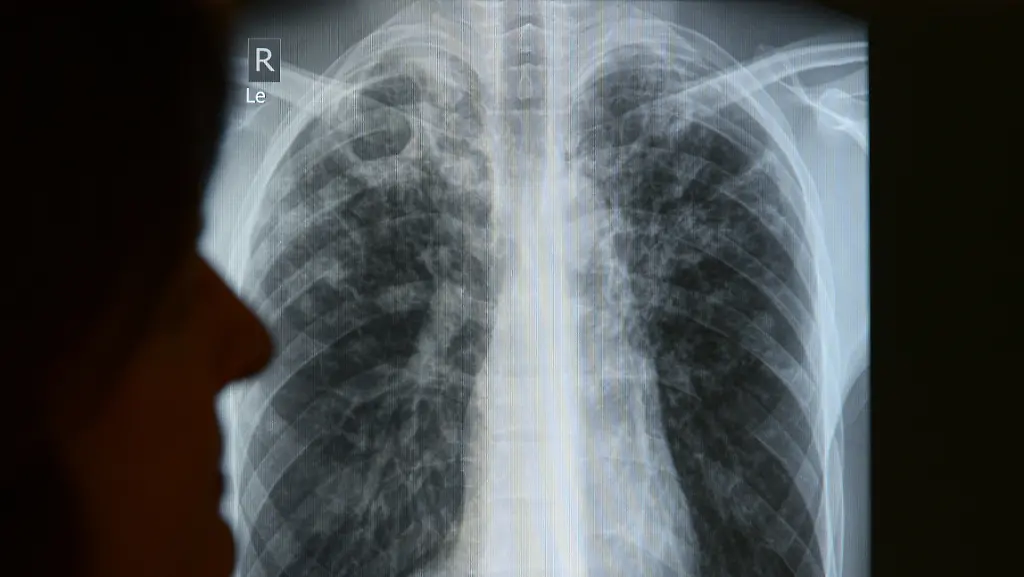

Tuberkulose-Erreger befallen am häufigsten die Lunge. 2013 starben weltweit 1,5 Millionen Menschen an den Folgen von Tuberkulose.

(Foto: picture alliance / dpa)